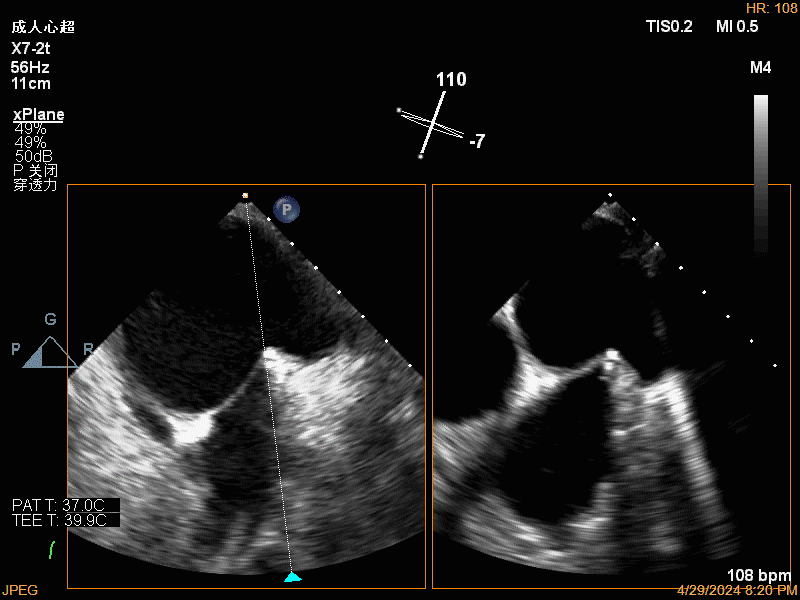

团队在反流最严重的2区精准植入1枚二尖瓣夹,即刻反流下降至微量,血压即刻上升20mmHg,跨瓣压差不升反降,由3mmHg降至2mmHg,改善效果明显,手术仅耗时一个半小时。 这是时隔四年继2020年指导开展区域内首例TAVR(经导管主动脉瓣置换)手术之后,陈茂教授再次带领华西团队,指导开展内自同城区域首例TEER术。陈茂教授对四院心内科心超图像的采集、房间隔穿刺的技巧、手术流程细节的把握、团队的默契配合、术前术后的管理表示称赞,鼓励四院心内科再接再厉造福区域患者。 患者为71岁老年女性,反复出现心累、气促已经超过10年,10多年来心衰的症状逐渐加重,间隔时间越来越短,且近1个月来已经3次因心衰住院,本次住院前已经无法耐受缓慢步行、如厕等日常生活,BNP超过了3000ng/ml。心电图为房颤,心超示左心室明显增大(65mm),重度二尖瓣反流(4+,CarpentierI+IIIb型),射血分数仅为31%。前叶长度:2.27cm且瓣尖增厚,后叶长度:1.14cm且局部钙化,瓣口面积:4.08cm2,反流宽度:1.7cm。患者及家属均拒绝外科开胸手术。 难点: 1.食道超声下该患者房间隔较厚较韧,且粗测高度仅为4.0cm,对穿刺的位置和技巧有较高要求; 2.左心扩大,反流宽度约17mm,放一个夹子可能不能有效解决反流,如放两个夹子需side by side 平行放置,但放置两个夹子有术后狭窄的风险; 3.前后叶对合似有间隙,若选用长宽夹子,会增加瓣叶张力,有瓣叶撕裂的风险,若选用短宽夹子,其捕获瓣叶的难度将增加; 4.患者心功能极差,手术需稳、准、快,不能耐受任何并发症风险。 影像资料 房间隔穿刺

![]() ![]() 瓣上瓣膜夹位置调整